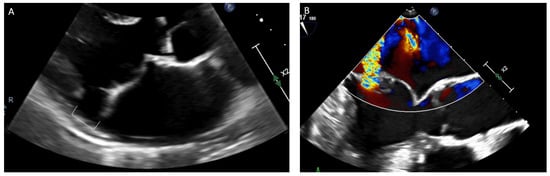

- Enriquez, A.; Shirai, Y.; Huang, J.; Liang, J.; Briceño, D.; Hayashi, T.; Muser, D.; Fulton, B.; Han, Y.; Perez, A.; et al. Papillary muscle ventricular arrhythmias in patients with arrhythmic mitral valve prolapse: Electrophysiologic substrate and catheter ablation outcomes. J. Cardiovasc. Electrophysiol. 2019, 30, 827–835. [Google Scholar] [CrossRef]